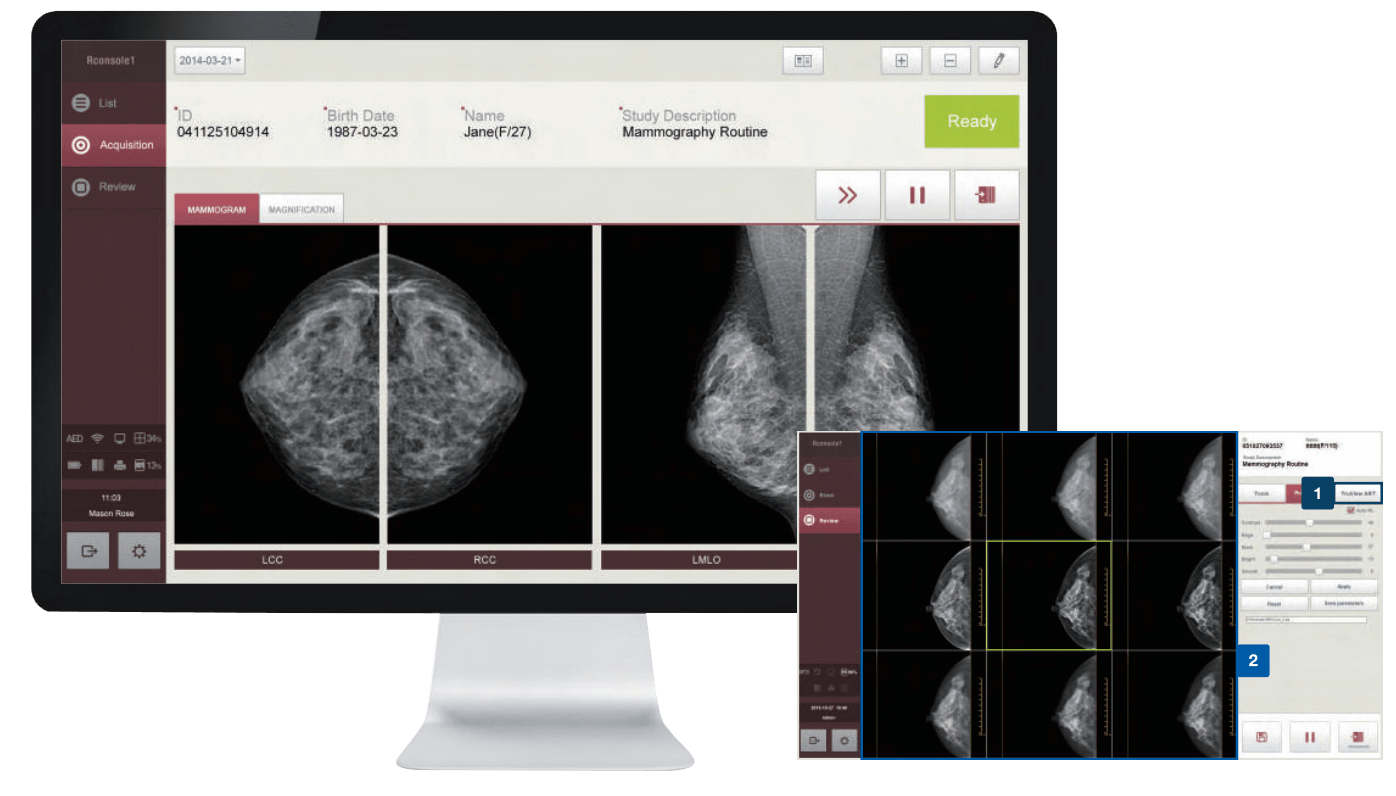

SISTEMA DE ADQUISICIÓN DE IMÁGENES

Práctico, cómodo e infaltable.

Potente PC protegida por una carcasa rígida y resistente, pantalla táctil, doble wifi, acompañada por la última versión del software de adquisicion EConsole1.

- Amplia variedad, para todas las prácticas.

- Repertorio completo de herramientas.

- La mejor calidad de imagen.

SOFTWARE

Innovador, intuitivo y fácil de usar

Cloud PACS

Almacenamiento de imágenes

Soluciones Avanzadas en la nube.

Procesamiento, medición, comunicación y almacenamiento de imágenes médicas. En cualquier momento y lugar !